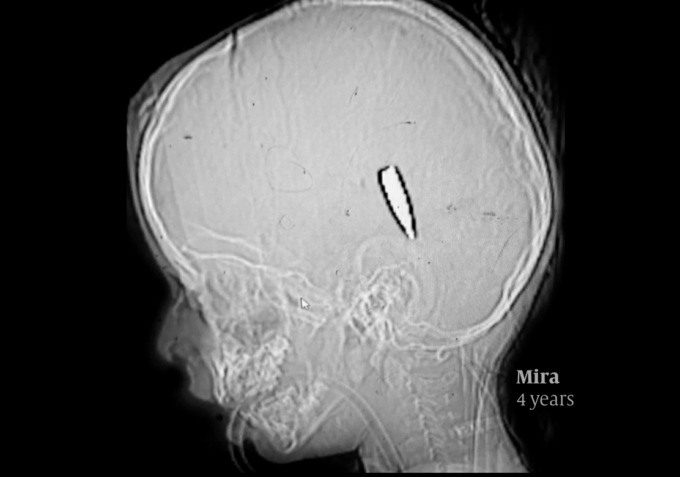

X-ray of Mira, a four-year-old Palestinian girl, shot in the head by an Israeli sniper. Photo: Mimi Sayed.

+ The Dutch newspaper De Volkskrant published a devastating new investigation into Israeli sniper attacks on Palestinian children. They consulted with 15 international doctors in a report finding that at least 114 Palestinian children were killed by single gunshot wounds to the head/chest. The forensic experts said the wounds are consistent with aimed fire. Two independent forensic pathologists, asked to review images and X-rays, said the injuries were consistent with bullets (not shrapnel). ’In all likelihood, these are distance shots aimed at the head and/or neck with military ammunition,’ says forensic pathologist Wim Van de Voorde, emeritus professor at the University of Leuven.